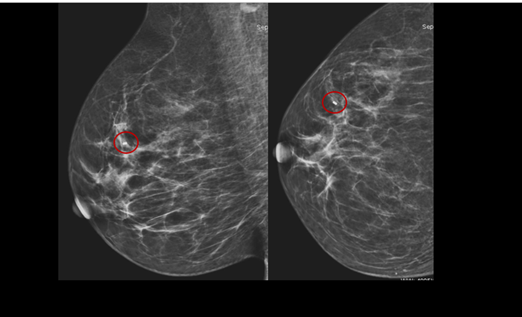

Esse é um dos tipos de biópsia de mama. A sua indicação mais comum é na

investigação de microcalcificações suspeitas na mamografia. Mas também pode ser

solicitada na presença de distorções, assimetrias e nódulos de pequenas

dimensões.

Pode ser realizada guiada pela mamografia (quando a lesão a ser pesquisada só aparece na mamografia) ou pela ultrassonografia.

Após a confirmação da saída das microcalcificações é importante a marcação do local biopsiado com um clipe metálico.